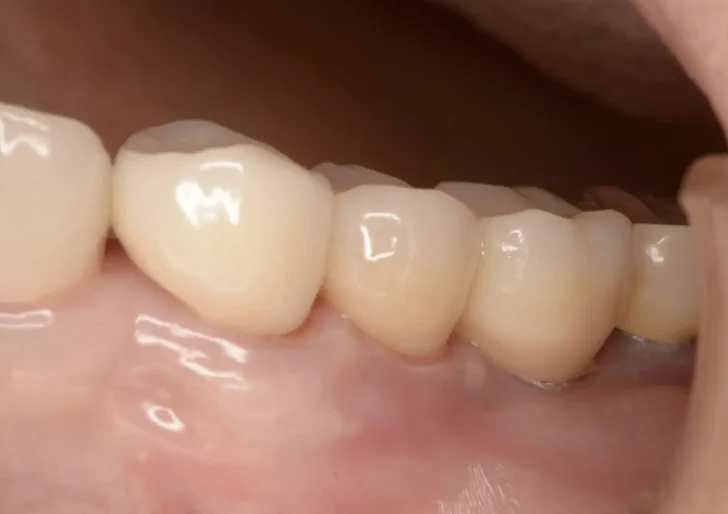

Before

After

銀歯の詰め直し(e-max)(50代女性)

約1ヶ月 3回 / 総額120,000円リスク・副作用:噛み合わせや歯ぎしりが強すぎる場合、セラミックが割れてしまう可能性があります。